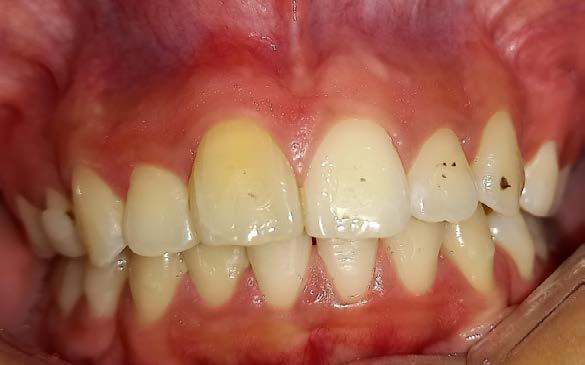

Figura 2. Imagen representativa de una luxación extrusiva en el órgano dental 11 que presenta un cambio de coloración en la encía.

necrosis pulpar. Las lesiones por luxación extrusiva requieren un tratamiento inmediato, consistente en reposicionamiento y estabilización. El tratamiento comienza con un correcto diagnóstico clínico y radiográfico, seguido del reposicionamiento manual del diente en el alvéolo y la colocación de una férula flexible, para permanecer in situ durante aproximadamente 2 semanas.6

Entre todas las lesiones orofaciales, las lesiones dentales traumáticas (TDI) son una de las más prevalentes. Representa el 18% de todas las lesiones en niños de 0 a 6 años (Figura 2) y Las lesiones por luxación se pueden clasificar en varios tipos según el grado de desplazamiento: conmoción cerebral, subluxación, luxación lateral, extrusión y avulsión. La raíz del germen del diente temporal y del permanente se encuentran muy cerca, por lo que las complicaciones a largo plazo de las TDL, como la infección de los dientes temporales, también pueden dañar los dientes sucesores en desarrollo. La prevalencia de lesiones por luxación es alta entre los niños pequeños debido a la naturaleza resistente de su hueso alveolar y sus estructuras de soporte (Figura 3). Se ha informado que las lesiones por intrusión causan más alteraciones de la mineralización en